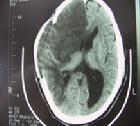

1.腦出血多在活動時或情緒激動時發病,多數有高血壓病史而且血壓波動較大,起病急,頭痛嘔吐意識障礙較多見,腦CT掃描可見高密度出血灶

1.腦CT掃描腦梗死的腦CT掃描的主要表現為:①病灶的低密度:是腦梗死重要的特徵性表現此徵象可能系腦組織缺血性水腫所致②局部腦組織腫脹:表現為腦溝消失腦池、腦室受壓變形,中線結構向對側移位即腦CT掃描顯示有占位效應此徵象可在發病後4~6h觀察到③緻密動脈影:為主要腦